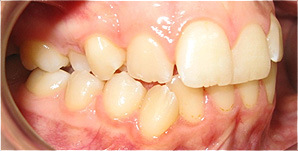

Apinhamento dentário com os dentes caninos em desoclusão (classe II, divisão 2).

![]() |

Após dois anos de tratamento ortodôntico.